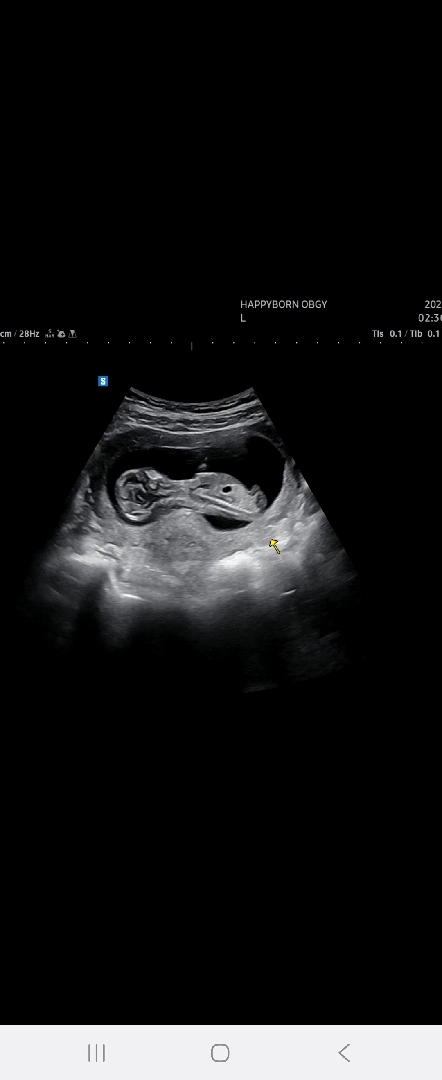

성별 각도법 알려주세요🩷

13주 된 예비엄마입니다ㅎㅎ 각도법으로도 성별을 알수있다는데 저는 잘 모르겠어요ㅠㅠㅎㅎ 아들이든 딸이든 상관없지만 그래도 너무너무 궁금하긴하네요!!

딸같아요!